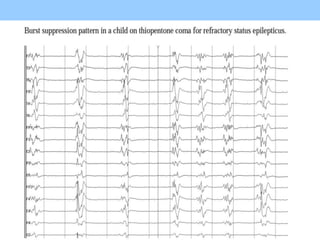

1. The document discusses EEG patterns and findings in various neurological conditions seen in children. It includes descriptions of normal EEG findings as well as abnormal patterns seen in conditions like absence seizures, West syndrome, benign childhood epilepsy with centrotemporal spikes, Lennox-Gastaut syndrome, non-convulsive status epilepticus, subacute sclerosing panencephalitis, and herpes encephalitis.

2. Case studies are presented with clinical histories and EEG findings to illustrate different pathologies. Treatment options are also mentioned for many of the conditions.